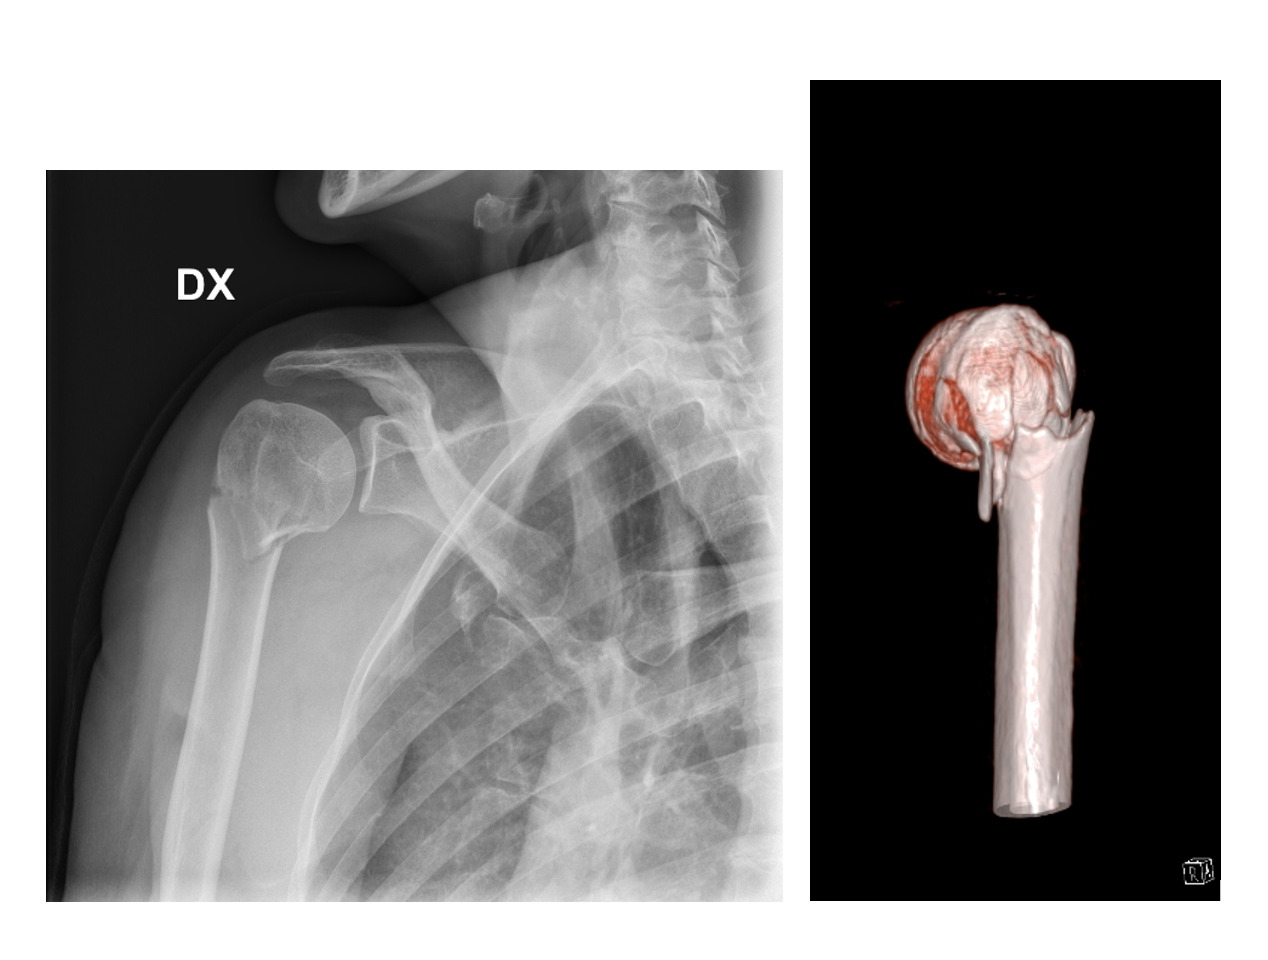

We identified eighty patients eligible for the study, according to the inclusion and exclusion criteria. Sixty-four patients (80%) were available for a telephonic evaluation, whether sixteen patients (20%) were lost at the follow-up and were excluded from the study. Mean age was 74 years (66-85). There were 19 males and 45 females. Mean follow-up was 4 years (1 to 7). Fracture types were classified according to Neer as two-part fracture in 6 cases (9%), as three-part fracture in 25 cases (39%), as four-part fracture in 33 cases (51%). According to the CV criteria, the severity grade was evaluated as low in 23 cases (36%), medium in 13 cases (20%) and high in 28 patients (44%). Fifteen patients (23,5%) were treated conservatively, with immobilization for 4 weeks before to start physiotherapy; forty-nine (76,5%) surgically. Three patients (4,5%) were treated with closed reduction and percutaneous osteosynthesis with Kirschner wires. One (1,5%) patient was treated with open reduction and synthesis with a locking plate. Nine patients (14%) were treated with an endomedullary autologous iliac crest bone graft and locking plate. Eight patients (12,5%) were treated with a titanium endomedullary cage and locking plate.18 Twenty-eight cases (44%) were treated with reverse prosthesis. In the immediate postoperative period, we did not observe any vascular complications. One patient need postoperative intensive care. In three patients we observed a postoperative temporary axillary palsy. Mean inpatient time was 3,5 days (±2,5). SST values are reported in table 1. The statistical regression test demonstrated that the severity grade (p<0,05) correlates better than the Neer classification (p=0,35) to the type of treatment. Indeed, no patient with a low severity grade was treated with a reverse prosthesis and the 85% of the conservatively treated patients are in the group graded as low severity grade. On the contrary, reverse prosthesis and conservative treatment were used with a similar frequency in 2-, 3- and 4- part fractures. In particular, we observed several 2-part fractures with high (Fig. 1) and medium (Fig. 2) severity grade characterized by calcar fracture and lateral comminution. On the other side, better SST values were not statistically associated to a lower severity grade neither to the Neer classification. Only if we calculate the SST values for a specific group of treatment we could find a significative correlation between severity grade and clinical outcomes.

The main finding of our study is that the use of Control Volume severity grade could help to define the stability and the complexity of proximal humerus fracture and, consequently, the better type of treatment. The therapeutical choice, of course, should take into account also several patients factors, such as: age, functional requests, comorbidities, expectative.19 Another important aspect of our study, is that displaced proximal humeral fractures cannot be evaluated just with plain radiographs, even if performed with the trauma series views. The use of a CT-scan and of a 3D model evaluation let the surgeon knows the real position of the humeral head, the measurement of anterior or posterior head tilting, the percentage of bone loss of the calcar. The amount of comminution is a key point, especially when referred to the calcar. Calcar comminution significantly decreases the stability of fracture reconstruction and gives direct information on the technical demand of fracture repair. On the other side, the Control Volume classification has some critical points. First, it is difficult to calculate the accurate topographic evaluation of bone loss without the help of specific researchers. Second, similar head displacement with equivalent bone loss could be associated with different severity, due to high comminution or different topographical involvement. This means that, the Control Volume measurements are not easy to evaluate and requires experts support. However, we believe that the spread of this preoperative study of the fracture, could reduce the tendency to treat indiscriminately with a reverse prosthesis all the displaced proximal humerus fracture associated to bone loss. According to the Control Volume severity grade, even fractures characterized by significant fragments displacement with posterior and superior displacement of the greater tuberosity equal or superior to 5 mm, could be treated non-operative, if the humeral head remains in a neutral position. The use of conservative treatment and of osteosynthesis, for the right fracture type, could reduce the complication, historically observed with these types of treatment, especially in case of bone fragility.10–12 We believe that previous studies demonstrating no difference between conservative and surgical treatment have not specifically assessed the type of fracture. The PROHFER study, for example, assessed only the surgical neck fracture by plain radiographs.5,6 Finally, the Control Volume criteria and the severity grade, in our series could predict the clinical outcome for patients treated with the same procedure. For patients treated with reverse prosthesis, the clinical outcomes are directly related to the healing of the tuberosities around the prosthetic stem. One of the factors influencing the severity grade is the multi-fragmentation of the greater tuberosity. In fact, in these cases, despite the accurate reconstruction of the tuberosity and the use of bone chips to fill the interface between cortical tuberosity and prosthesis, the external rotation was less effective than when the great tuberosity is intact or with a large fragment.20 This study has several weaknesses: it is a retrospective study, including a relatively small number of patients. The use of Control Volume criteria should be tested in prospective multicentric observational studies.